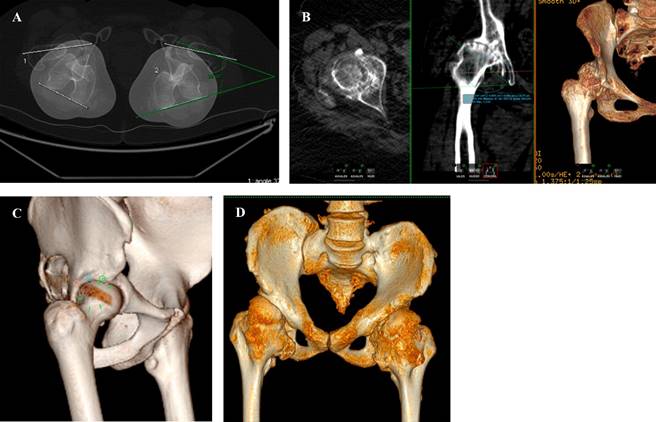

Tomografía axial computarizada (TAC)

La TAC es de utilidad en el abordaje de cadera dolorosa para evaluación de la capa I de Kelly, es decir, el componente óseo del par fémur-acetábulo (conflictos de espacio o inestabilidad). A pesar de que su utilidad es mayor en el caso de trauma agudo, la reconstrucción tridimensional y con cortes finos ha formado parte de la evaluación básica de deformidades simples y complejas, como problemas relacionados con las versiones tanto acetabulares como torsiones del cuello femoral; la anteversión femoral se define como el ángulo en el eje axial formado entre el cuello femoral y la superficie posterior de los cóndilos femorales, su valor normal en el adulto es de 8 a 15o.15

Gracias a este estudio podemos determinar ángulos y medidas tridimensionales como el ángulo de McKibbin, el cual es una combinación entre la anteversión femoral y acetabular y de utilidad como predictor de inestabilidad de la cadera (> 60o) o de pinzamiento (< 30o), como claro ejemplo de la evaluación y abordaje clínico y terapéutico de las patologías que provocan coxalgia (Figura 14).15,18

Figura 14: A) Medición de anteversión de caderas con respecto a cóndilos femorales. B) Coxartrosis izquierda secundaria a displasia de cadera con ascenso de centro de rotación. C) Deformidad de cabeza femoral tipo cam. D) Paciente con osteocondromatosis múltiples que le generan pinzamientos extraarticulares en diferentes sitios anatómicos.